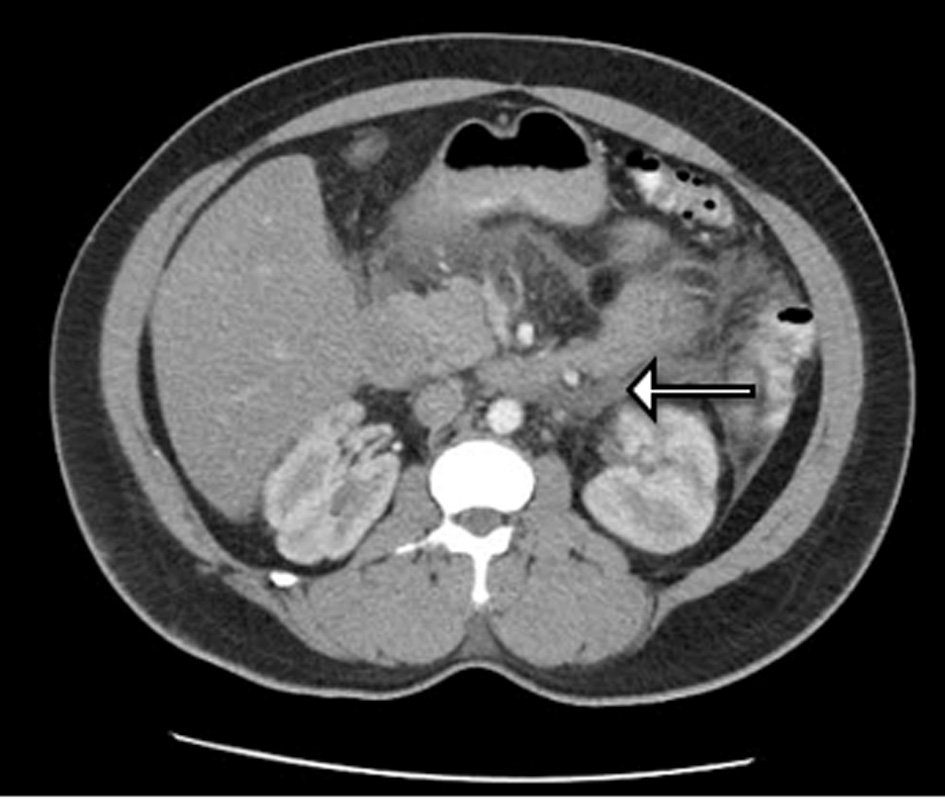

Further analysis included computed tomography scan of the abdomen correlating with acute pancreatitis involving the head, uncinate process and pancreatic duodenum but no pancreatic ductal dilatation or obvious calcification (Fig. 1). Right upper quandrant ultrasound was also completed; however, it was found to be unremarkable.

![]() Click for large image | Figure 1. CT of abdomen demonstrating degree of pancreatitis. |